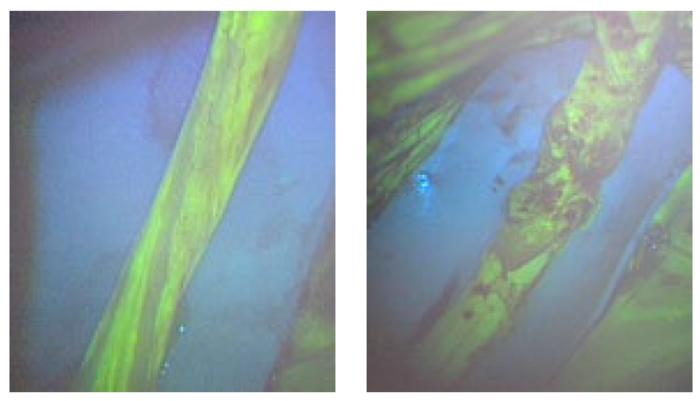

With this in mind, an Osaka Metropolitan University-led research team involving Graduate School of Medicine student Kosuke Saito and Associate Professor Mitsuhiro Okada investigated the use of fluorescein angiography, a method employed in neurosurgery and ophthalmology to highlight blood vessels, to visualize neural blood flow in chronic nerve compression neuropathies like carpal tunnel syndrome.

The team found that fluorescein angiography could detect a decrease in neural blood flow in rats and rabbits with chronic nerve compression neuropathy. The results also correlated with electrodiagnostic findings.

Then fluorescein angiography was used for human patients undergoing open carpal tunnel release surgery, and the data also correlated strongly with electrodiagnostic testing. The findings indicate that fluorescein angiography might possess high diagnostic capabilities to assess neural blood flow during surgery.